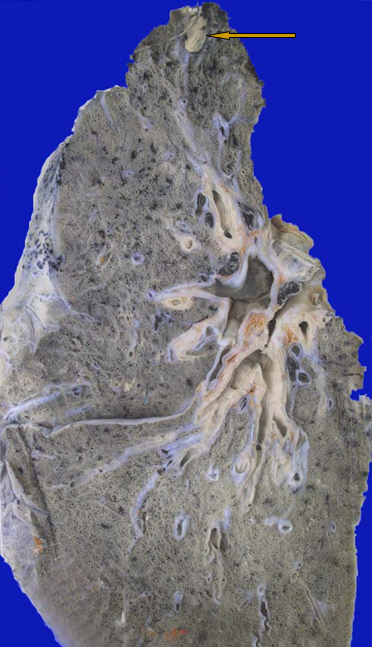

3.慢性纤维空洞型肺结核:又称开放性肺结核,是本病最主要的传染源!

病变特点:

①肺内有一个或多个厚壁空洞。多位于肺上叶,大小不一,不规则。

②同侧或对侧肺组织,特别是肺下叶可见由支气管播散引起的很多新旧不一、大小不等,病变类型不同的病灶。愈往下愈新鲜。

③后期肺组织广泛纤维化、胸膜增厚并与胸壁粘连,使肺体积缩小、变形。

厚壁空洞病理变化:

壁厚可达1cm,镜下:镜下洞壁由内到外可分三层,内层 为干酪样坏死物(含多量结核杆菌),中层为结核性肉芽组织,外层为纤维结缔组织。

结局:经治疗,空洞可机化、闭塞或开放性愈合。

后期硬化性肺结核----肺动脉高压----肺源性心脏病

临床表现:咳嗽、咳痰、咯血等症状,严重可出现气胸或脓气胸。痰中含有结核杆菌,可引起喉结核、肠结核。